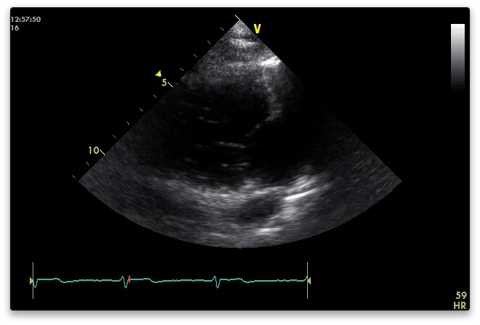

PRVI (parasternal RV inflow)

From the PLAX view tilt the probe anteriorly looking towards the patients right hip.

2D

Capture

Anterior (upper) and posterior (lower) tricuspid valve leaflets.

RA, RV, IVC +/-coronary sinus also visible.